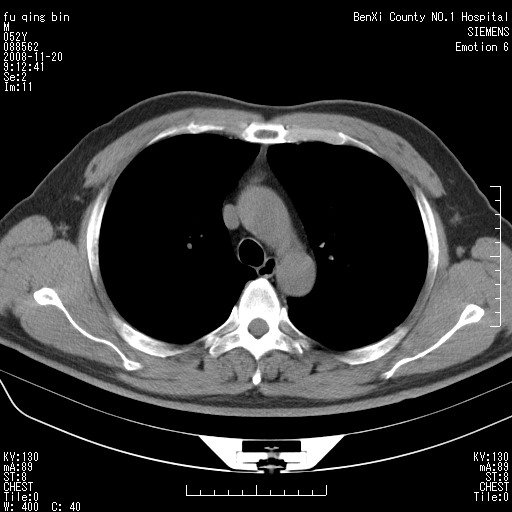

男、52、胸闷不适。前纵隔可见结节影,ct值16hu左右。大家帮忙看看如何诊断

升主动脉前方之新月形影,边缘光滑,密度较低,ct值较低,考虑心包上隐窝